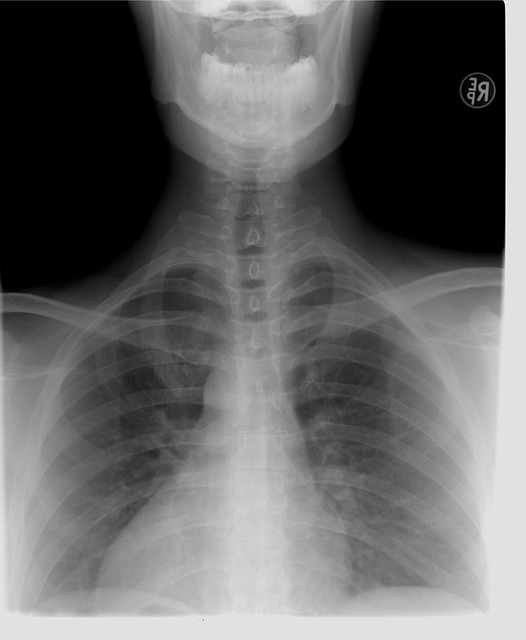

Skolióza páteře

Je opravdu hodně smutné, pokud vás bolí záda, já tohle moc dobře znám. Nejsem už nejmladší, ale také nejsem samozřejmě nejstarší, ale řeknu vám, že někdy ta bolest zad je opravdu hrozná. Někdy ta bolest zad je opravdu neúnosná. Mám bohužel skoliózu páteře, skoliózu, páteře mi zjistili, když mi bylo sedmnáct let. Ještě jsem nebyla ani plnoletá a už jsem měla problémy se zády. Moje maminka tomu nemohla stále uvěřit a stále dokola se ptala pana lékaře. Jestli se třeba nespletl, že já rozhodně nemůžu mít skoliózu páteře, maminka si to myslela, protože jsem závodně dělala aerobik a také jsem plavala a říkala si, že rozhodně nemůžu mít žádné zdravotní problémy a už vůbec ne skoliózu páteře.